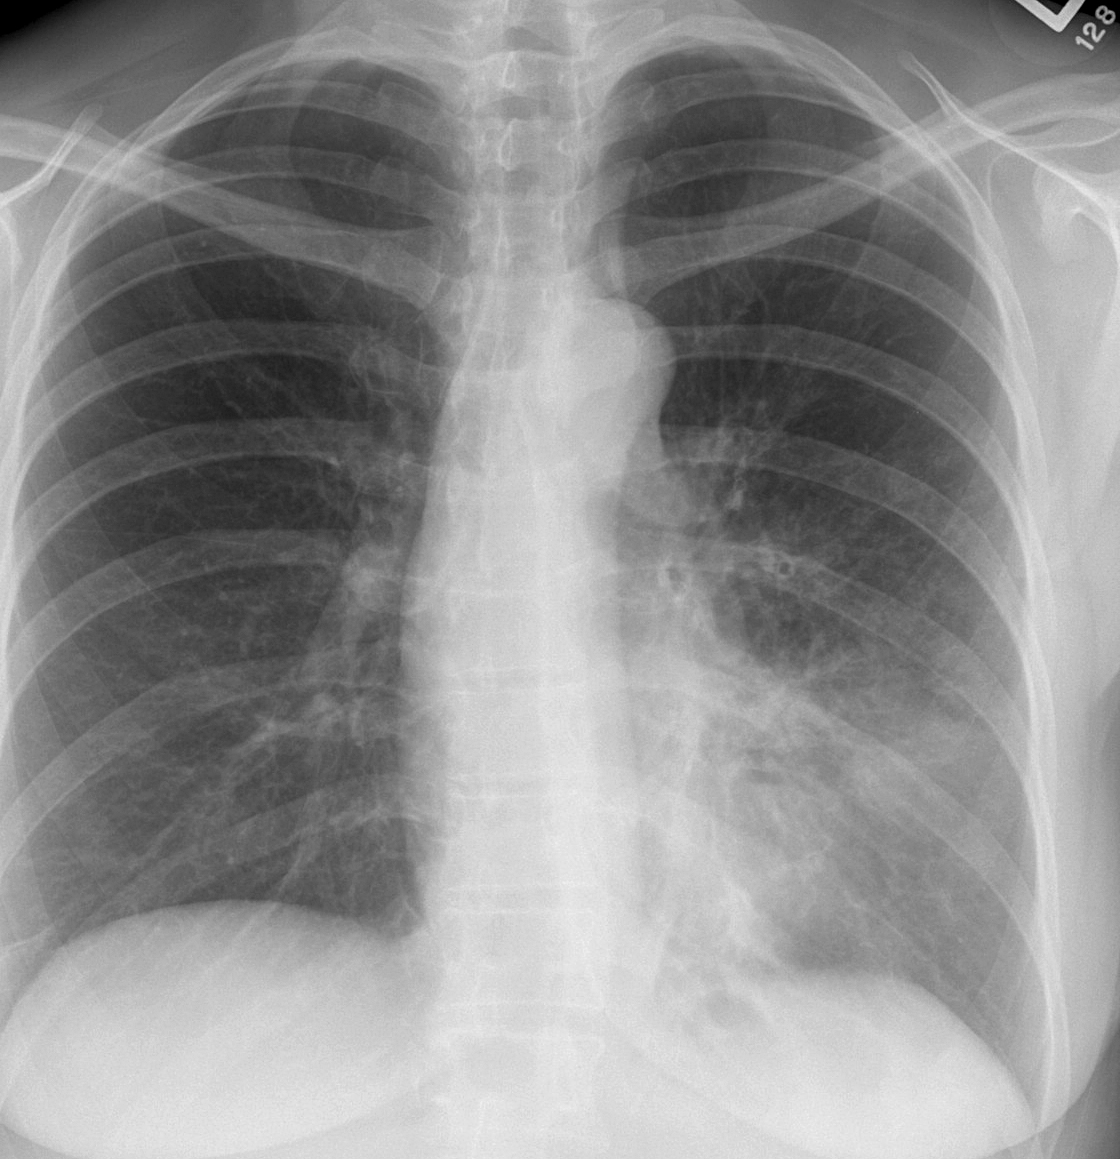

Lingular pneumonia PA

Date: 10/15/2006